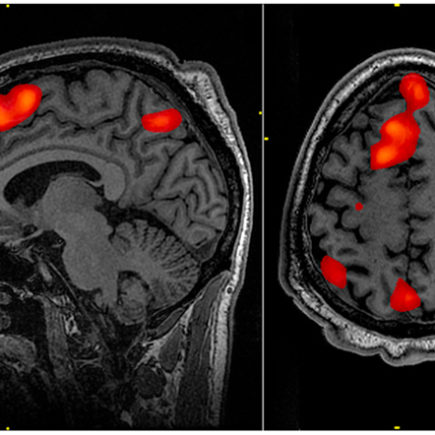

Alivia tu depresión en un 90% con estimulación magnética

UN NUEVO TRATAMIENTO DE ESTIMULACIÓN MAGNÉTICA ALIVIA LA DEPRESIÓN EN EL 90% DE LOS PACIENTES Por Tess H. Santacreu Un nuevo tratamiento de estimulación magnética transcraneal, en altas dosis y focalizada, consiguió aliviar los síntomas en la mayoría de los pacientes con depresión grave La estimulación magnética transcraneal (TMS) se usa habitualmente para el tratamiento de los pacientes con depresión severa, pero sólo la mitad consiguen mejorar, y únicamente la tercera parte remite. Con el nuevo tratamiento desarrollado por investigadores de la Escuela de Medicina de la Universidad de Stanford (California) se ha perfeccionado esta técnica y se han mejorado mucho sus resultados. …